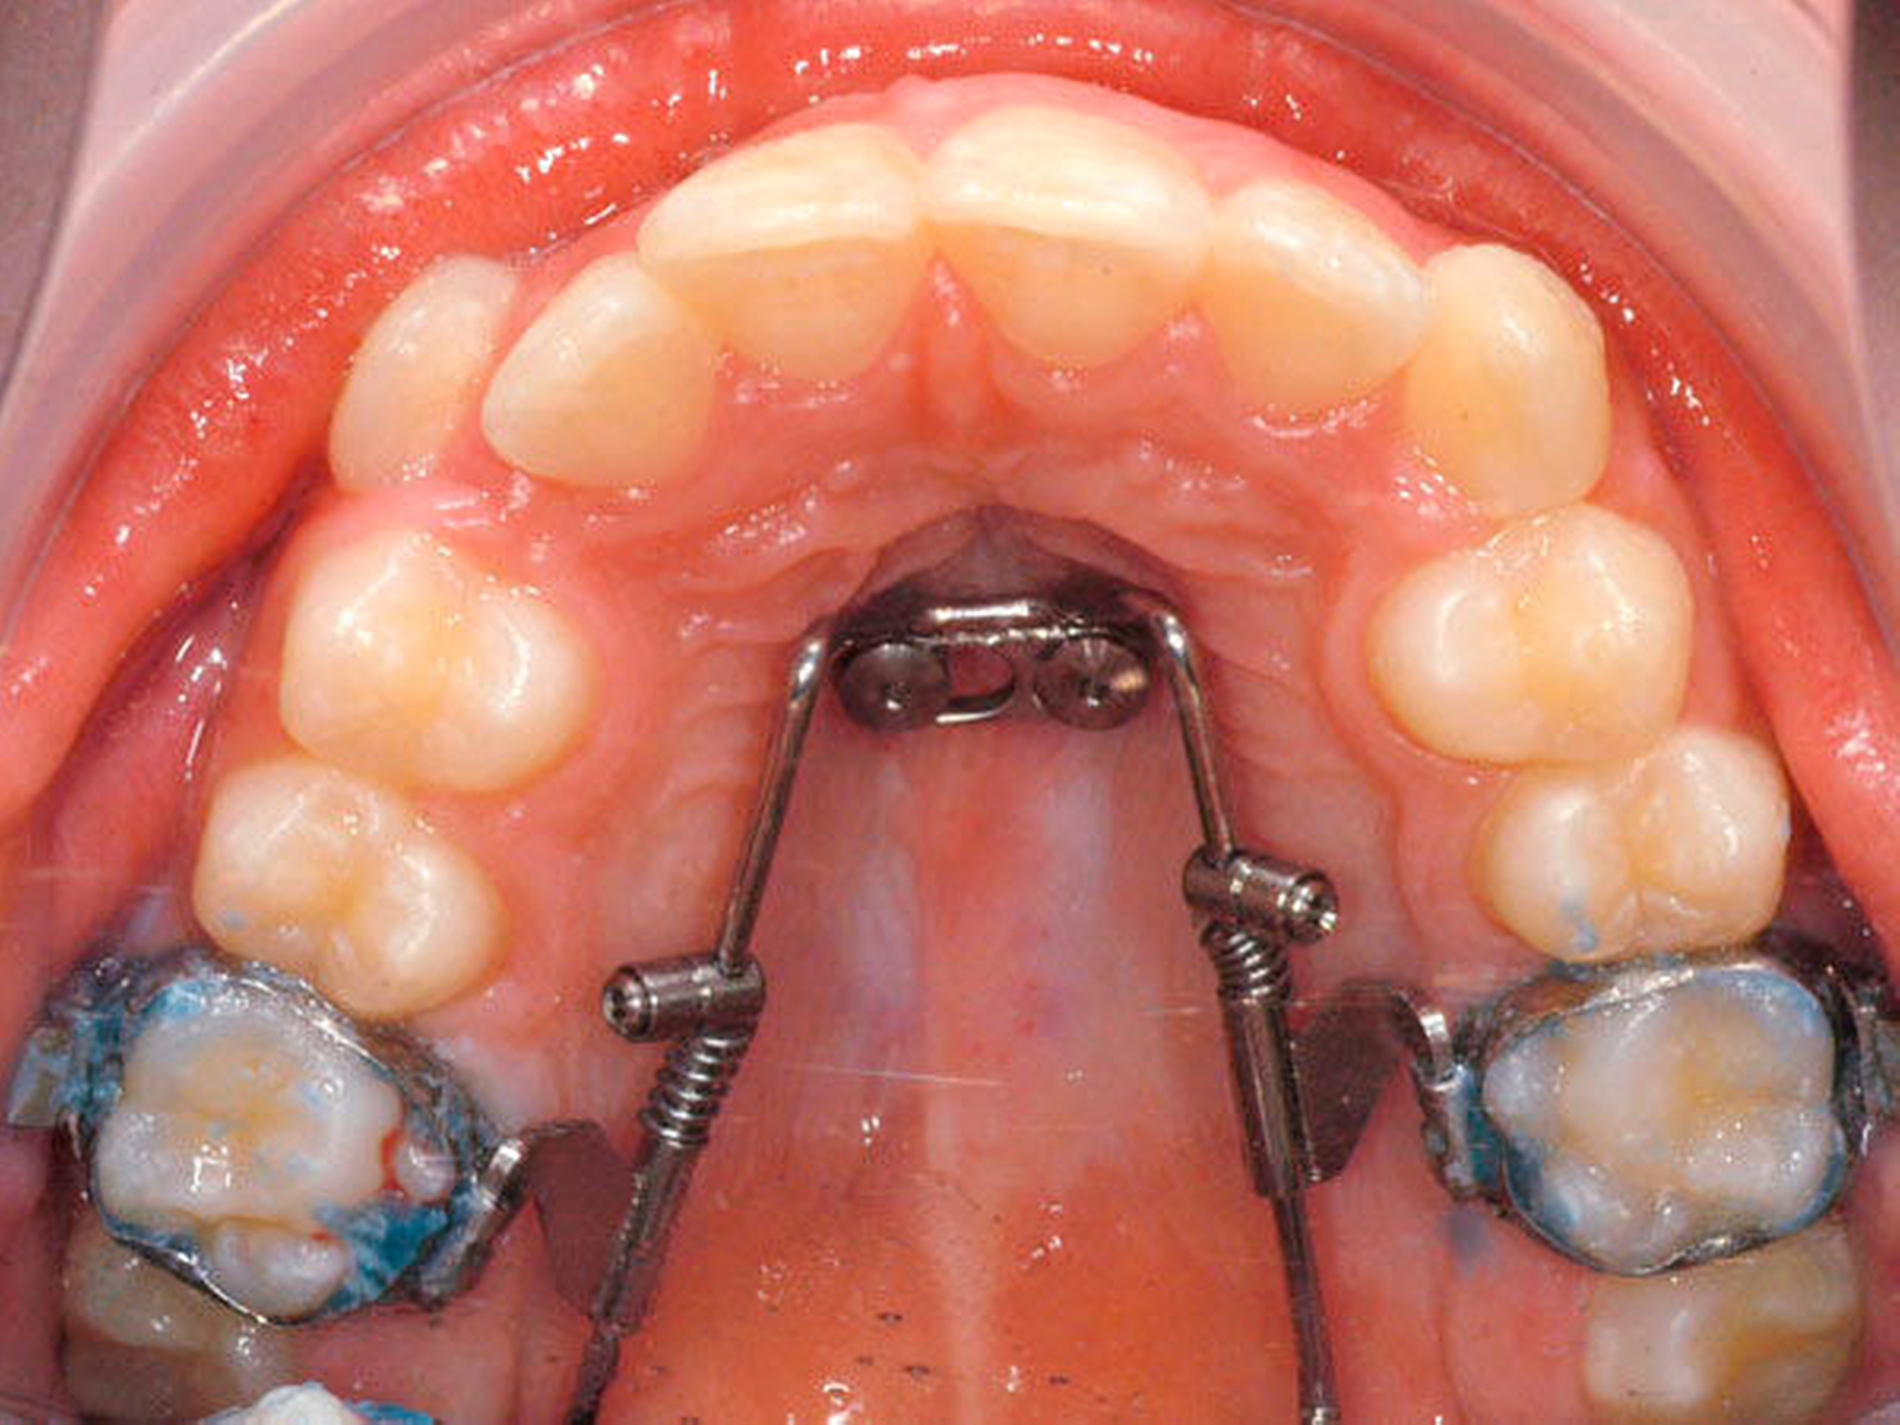

Das Prinzip einer CAD/CAM-gesteuerten Insertion wird anhand einer zehnjährigen Patientin mit einem Platzmangel für die oberen Eckzähne dargestellt (Abbildungen 4a, 4b). Die Behandlung begann mit dem Anpassen von Molarenbändern und einem Silikon-Abdruck des Oberkiefers, der mit dem FRS an das zahntechnische Labor gesendet wurde und dort mit dem FRS der Patientin überlagert wurde. So konnten geeignete Insertionsstellen virtuell geplant werden (Abbildungen 1, 2a, 2b). Nach Rücksprache mit dem Behandler bezüglich der Mini-Implantatpositionen erfolgte die Herstellung der Insertionsschablone (Abbildung 3). Parallel dazu wurde auch der Beneslider [Wilmes, 2010] hergestellt, der zusammen mit der Insertionsschablone geliefert wurde (Abbildung 5). Mithilfe der Insertionsschablone konnten die Mini-Implantate und der Beneslider im selben Termin eingesetzt werden (Abbildungen 6, 7a, 7b). Nach 10 Monaten Distalisierung waren die Molaren in der Zielposition und es war ausreichend Platz für die Eckzähne vorhanden (Abbildungen 8a, 8b), so dass Brackets für die zweite Phase der Behandlung eingesetzt werden konnten. Die Multibracket-Apparatur (Abbildung 9) konnte nach 12 Monaten entfernt werden (Abbildungen 10, 11).